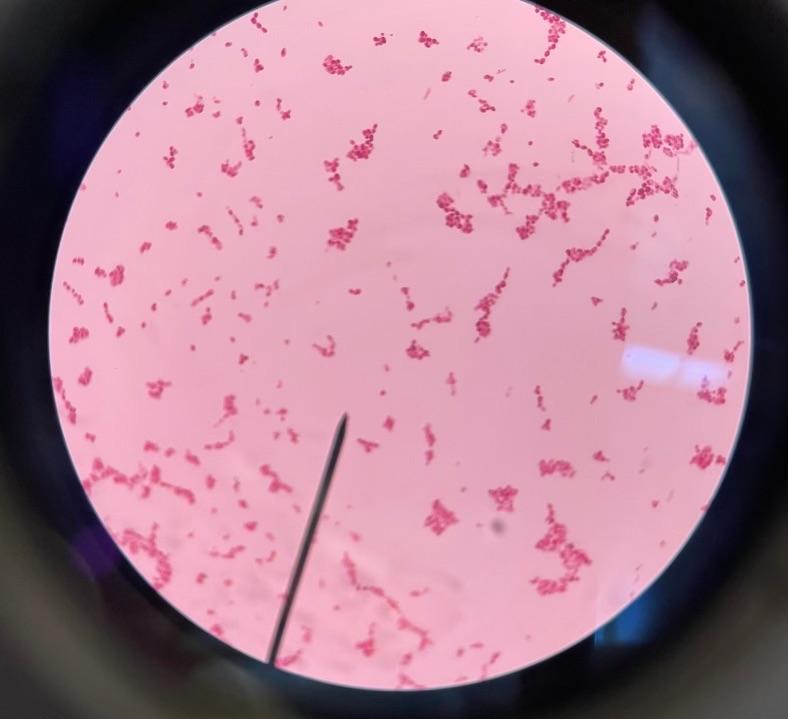

Trypanosoma gambeinse (blood smear)